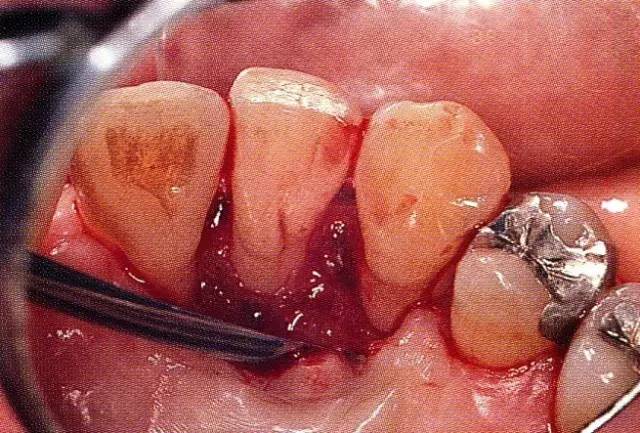

640.webp (3).jpg

▲圖7-4  術(shù)后1年2個(gè)月再翻開看的情況。與圖7-1的骨缺損狀態(tài)相比可知形成了臨床性骨再生。

640.webp (4).jpg

▲圖7-5  此狀態(tài)下,左下5的遠(yuǎn)中存在牙槽骨不平整,因此進(jìn)行了骨修整。同時(shí),將骨膜留存,進(jìn)行了齦瓣根尖側(cè)移動(dòng)術(shù),去除了牙周袋。